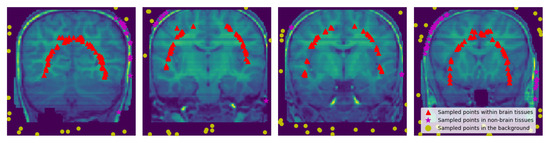

2.2.3. Sampling Points within the Brain, Non-Brain Tissues and Background